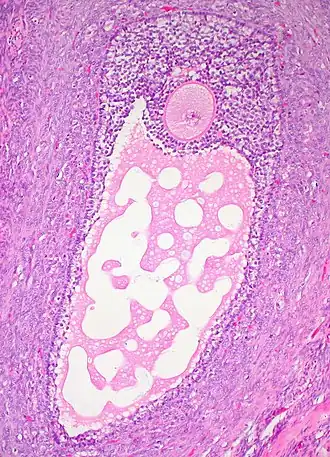

![]() Histology section of a mature ovarian follicle. The oocyte is the large, round, pink-staining cell at top center of the image. | |

An ovarian follicle is a roughly spheroid cellular aggregation set found in the ovaries. It secretes hormones that influence stages of the menstrual cycle. In humans, women have approximately 200,000 to 300,000 follicles at the time of puberty,[1][2] each with the potential to release an egg cell (ovum) at ovulation for fertilization.[3] These eggs are developed once every menstrual cycle with around 300-400 being ovulated during a woman's reproductive lifetime.[4]

Ovarian follicles are the basic units of female reproductive biology. Each of them contains a single oocyte (immature ovum or egg cell). These structures are periodically initiated to grow and develop, culminating in ovulation of usually a single competent oocyte in humans.[5] They also consist of granulosa cells and theca of follicle.

Once a month, one of the ovaries releases a mature egg (ovum), known as an oocyte. The nucleus of such an oocyte is called a germinal vesicle[6] (see picture).